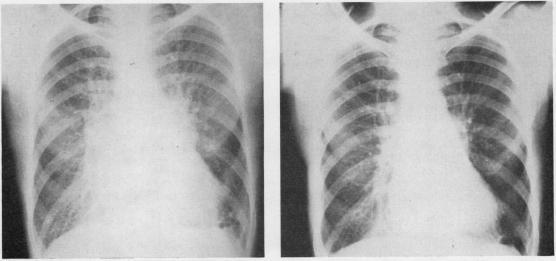

The first 16 patients to have mitral valve replacement with the Starr-Edwards prosthesis at St. Bartholomew's Hospital, London, were reviewed from one to three years after operation. These patients had presented with serious mitral valve disease and there was a high incidence of severe dyspnoea and persistent congestive failure before operation. There were four operative deaths, and two survivors had poor results due to regurgitation alongside the prosthesis. The remaining 10 patients showed considerable improvement. Although no diuretics were given after operation there was little dyspnoea and congestive failure resolved. Anticoagulant therapy is given after operation, and there have been few embolic incidents. The pulmonary vascular resistance was raised to between 6 and 11 units before operation in six patients. There was no undue mortality in this group, and post-operative cardiac catheterization showed a considerable fall in resistance and an increase in cardiac output, suggesting resolution of the pulmonary vascular obstruction. Tricuspid incompetence in these patients disappeared post-operatively. We conclude that mitral valve replacement can restore a patient severely disabled by mitral valve disease to a nearly normal life. We do not regard pulmonary hypertension as a contraindication to operation.

对伦敦圣巴塞洛缪医院首批16例使用斯塔尔-爱德华兹人工瓣膜进行二尖瓣置换术的患者进行了术后1至3年的随访。这些患者均患有严重的二尖瓣疾病,术前重度呼吸困难和持续性充血性心力衰竭的发生率很高。手术死亡4例,2例幸存者因人工瓣膜旁反流效果不佳。其余10例患者有明显改善。术后未使用利尿剂,呼吸困难轻微,充血性心力衰竭得到缓解。术后给予抗凝治疗,栓塞事件很少。6例患者术前肺血管阻力升至6至11单位。该组患者无过高死亡率,术后心导管检查显示阻力显著下降,心输出量增加,提示肺血管阻塞得到缓解。这些患者的三尖瓣关闭不全术后消失。我们得出结论,二尖瓣置换术可使因二尖瓣疾病严重致残的患者恢复到接近正常的生活。我们不认为肺动脉高压是手术的禁忌症。